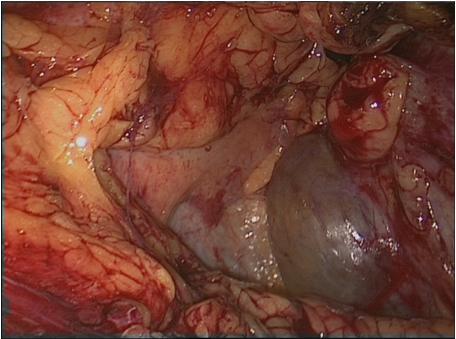

Derzeit zählen Adrenalektomie, Nephrektomie, Nephrourterektomie, Lymphozelenfensterung, Varikozelenlegatur, Nierenzystenabtragung usw. Bei der laparokopischen Nierenzystenresektion (Abbildung 2 [Abb. 2], Abbildung 3 [Abb. 3]) bietet diese Möglichkeit dem Operateur eine hervorragende Übersicht mit der Möglichkeit eine Schnellschnittdiagnostik durchzuführen sowie eine minimal-invasive Methode für die Patienten, die nach 2 Tagen entlassen werden können.

Abbildung 3: Laparoskopische Nierenzystenresektion